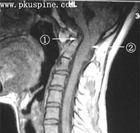

扁平顱底是顱頸區較常見的先天性骨畸形,單獨存在時一般不出現症狀,常與顱底凹陷症並發。本病患者顱中窩、顱前窩底部和顱底斜坡部均向顱內凹陷,使顱底角大於145°,具有診斷意義。

診斷主要根據顱骨側位片測量顱底角(蝶鞍與斜坡形成角度),顱骨側位片由鼻根至蝶鞍中心連線與蝶鞍中心向枕大孔前緣連線形成的夾角,成人正常值為109°-145°,平均132°。本病患者顱中窩、顱前窩底部和顱底斜坡部均向顱內凹陷,使顱底角大於145°,具有診斷意義。